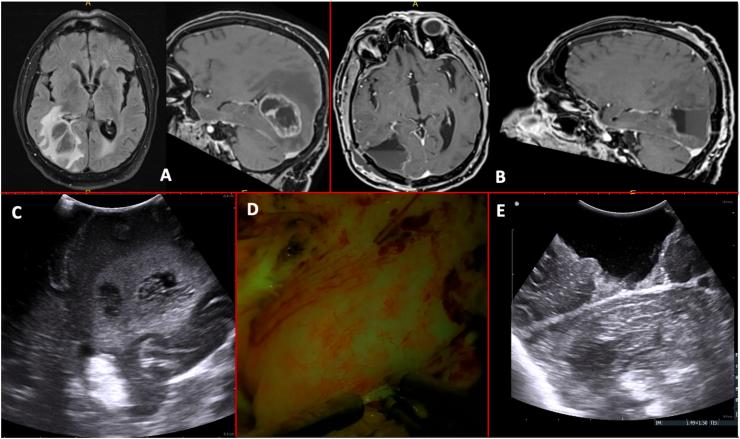

High-Grade Gliomas are the most common primary brain malignancies and despite the multimodal treatment, and the increasing amount of adjuvant treatment options the overall prognosis remains dismal. The present investigation aims to analyze the safety profile of the use of intraoperative ultrasounds (Io-US) in a homogeneous and matched cohort of patients suffering from High-grade gliomas (HGG) operated on with or without the aid of Io-US and Fluorescein in specific relation to the incidence of neurological and functional status sequelae.

A retrospective analysis was performed on 74 patients affected by HGG. 22 patients were treated with Io-US matched with neuronavigational system (Group A); 15 patients were treated both with the use of Io-US and Fluorescein matched with neuronavigational system (Group B); 37 patients were treated with the use of the neuronavigational system only (Group C). Primary endpoints were the extent of resection and functional outcome (measured with Karnofski Performance Status).

Significative differences were observed in terms of a higher extent of resection in Group B. In a multivariate analysis, this data appears to be independent of the location (eloquent/non-eloquent) of the lesion and from its histology. Regarding functional outcomes, no differences were detected between the two groups.

The present study is the first that analyzes the simultaneous use of Io-US and Fluorescein, and the results demonstrate that these two instruments together could improve the extent of resection in HGG while ensuring good outcomes in terms of functional status.